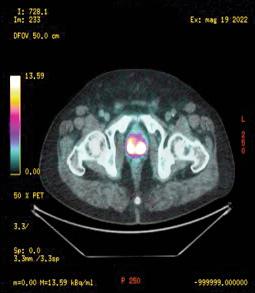

Figure 1

68Ga prostate specific membrane antigen (PSMA) PET/CT: presence of high suspicious area fo prostate cancer (SUVmax 20) in both lobe of the prostate (axial evaluation)

was performed from the skull base to the middle of the thigh Images were processed to obtain PET, CT, and PET CT fusion sections in the axial, coronal, and sagittal planes with a thickness of approximately 0 5 cm by two experienced nuclear medicine specialists, who were blinded to the clinical data The location of focal uptake on 68Ga PSMA PET/TC (Figure 1), three dimensional size, and standardised uptake value (SUVmax) values were reported on a per lesion basis with a sexstant scheme (apex, midgland, and base, each split into left and right) (5) All mpMRI (Prostate Imaging Reporting and Data System “PI RADS” version 2 ≥ 3) and 68GaPSMA PET/CT (SUVmax > 5 g/ml) index lesions underwent targeted cores (mpMRI TPBx and PSMA TPBx: four cores) com bined with extended systematic prostate biopsy (eSPBx: median 18 cores) (2, 14) The procedure was performed transperineally using a tru cut 18 gauge needle (Bard, Covington, GA, USA) under sedation and antibiotic pro phylaxis (17) Prostate targeted cores were obtained using a Hitachi 70 Arietta echograph (Chiba, Japan) supplied by a bi planar trans rectal probe (14) by one urologist with 10 years of experience in cognitive targeted biopsy Data were collected following START criteria (18)